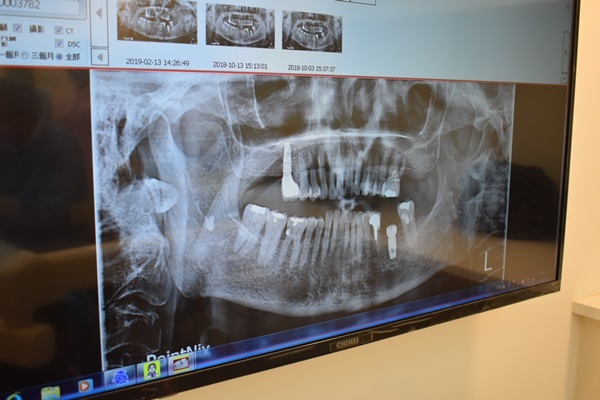

不過骨質密度狀況不錯醫師建議可以微創植牙

去年媽咪在牙醫診所做的微創植牙到上個月底剛好滿一年

給醫師檢查完之前植牙的地方後

醫師說媽咪植牙的地方顧得很好沒什麼蛀牙

牙齒也算健康乾淨~沒有牙結石

若要做牙齒美白絕對沒問題